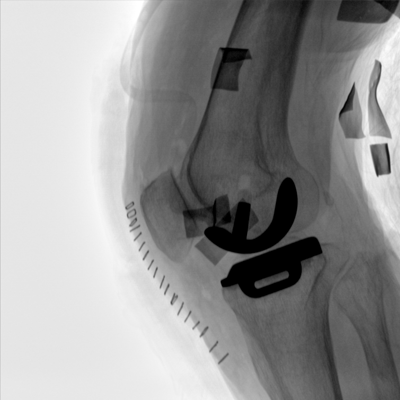

大尺寸動態(tài)平板探測器,高DQE、低噪聲、圖像清晰。采用多分辨率圖像增強處理技術(shù),不同部位不同圖像處理算法,滿足客戶多樣化的需求。

采用智能變頻脈沖透視技術(shù),優(yōu)化圖像質(zhì)量的同時降低輻射劑量,呵護(hù)醫(yī)患健康